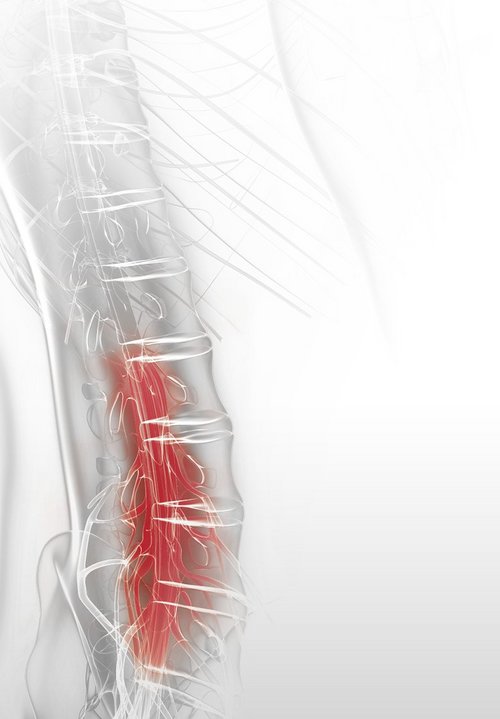

Lateral Recess Stenosis

The lateral recess stenosis causes compression of the traversing nerve root and lateral portions of the spinal cord. This is caused by a narrowing of the bony structures in the lateral recess of the spinal canal.

Surgical intervention involves precise bone resection via a full-endoscopic interlaminar approach using the VERTEBRIS L / X system. Steps include resecting the descending articular process and carefully opening the ligamentum flavum to expose and decompress the neural structures.